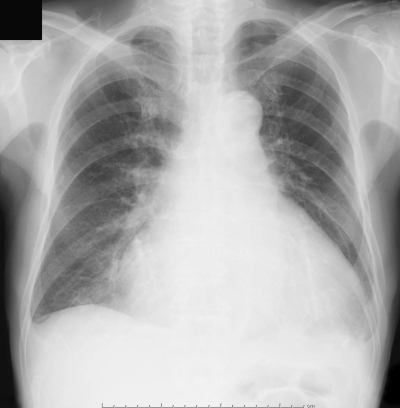

血液所見:赤血球459万、Hb 14.1g/dL、Ht 42%、白血球4,900、血小板19万。血液生化学所見:総蛋白7.6g/dL、アルブミン3.8g/dL、総ビリルビン1.1mg/dL、直接ビリルビン0.3mg/dL、AST 52IU/L、ALT 49IU/L、LD 420IU/L(基準176~353)、ALP 358IU/L(基準115~359)、γ-GTP 60IU/L(基準8~50)、アミラーゼ124IU/L(基準37~160)、脳性ナトリウム利尿ペプチド(BNP)478pg/mL(基準18.4以下)、尿素窒素16mg/dL、クレアチニン1.1mg/dL、Na 141mEq/L、K 4.0mEq/L、Cl 104mEq/L。CRP 1.3mg/dL。心電図と胸部エックス線写真とを別に示す。心エコーで左室駆出率44%であり、高度の僧帽弁逆流と下大静脈の拡大とを認める。 初期治療において投与するのはどれか。3つ選べ。